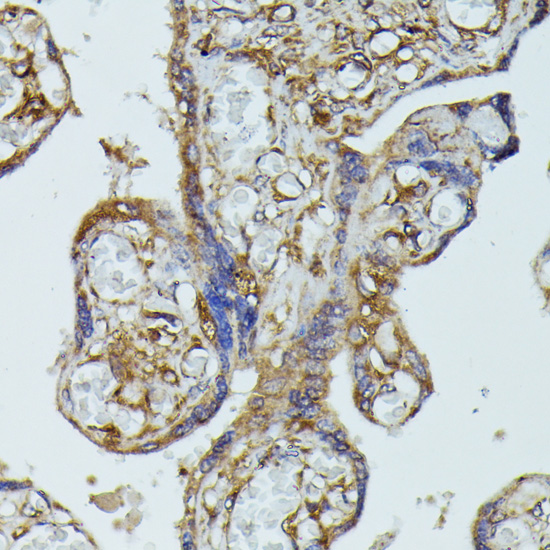

Immunohistochemistry of paraffin-embedded human placenta using FGD1 antibody.